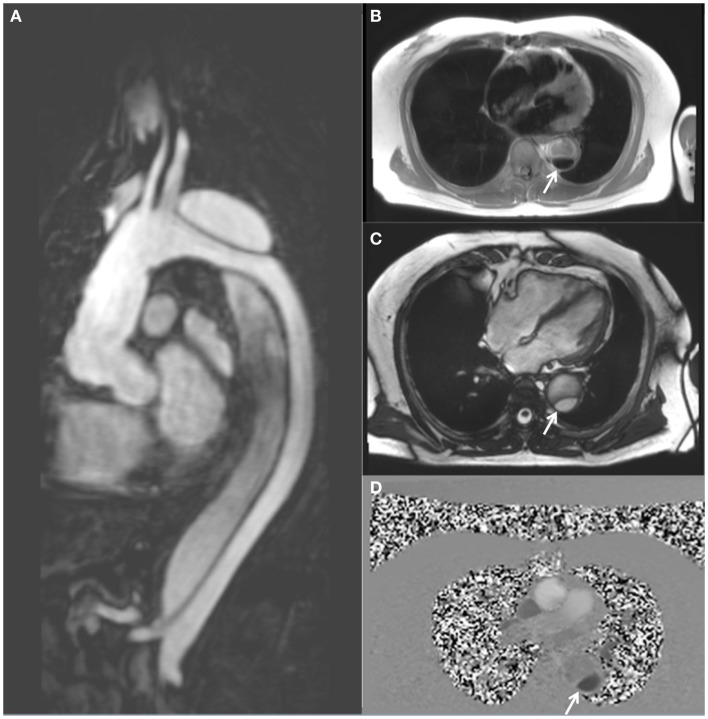

63岁,男性,胸主动脉夹层。(A)矢状位钆对比增强MRA图;(B)

黑血图;(C)TrueFISP电影图;(D)相对比图,显示降主动脉的真腔和假腔的流动模式,真腔由白色箭头指示。